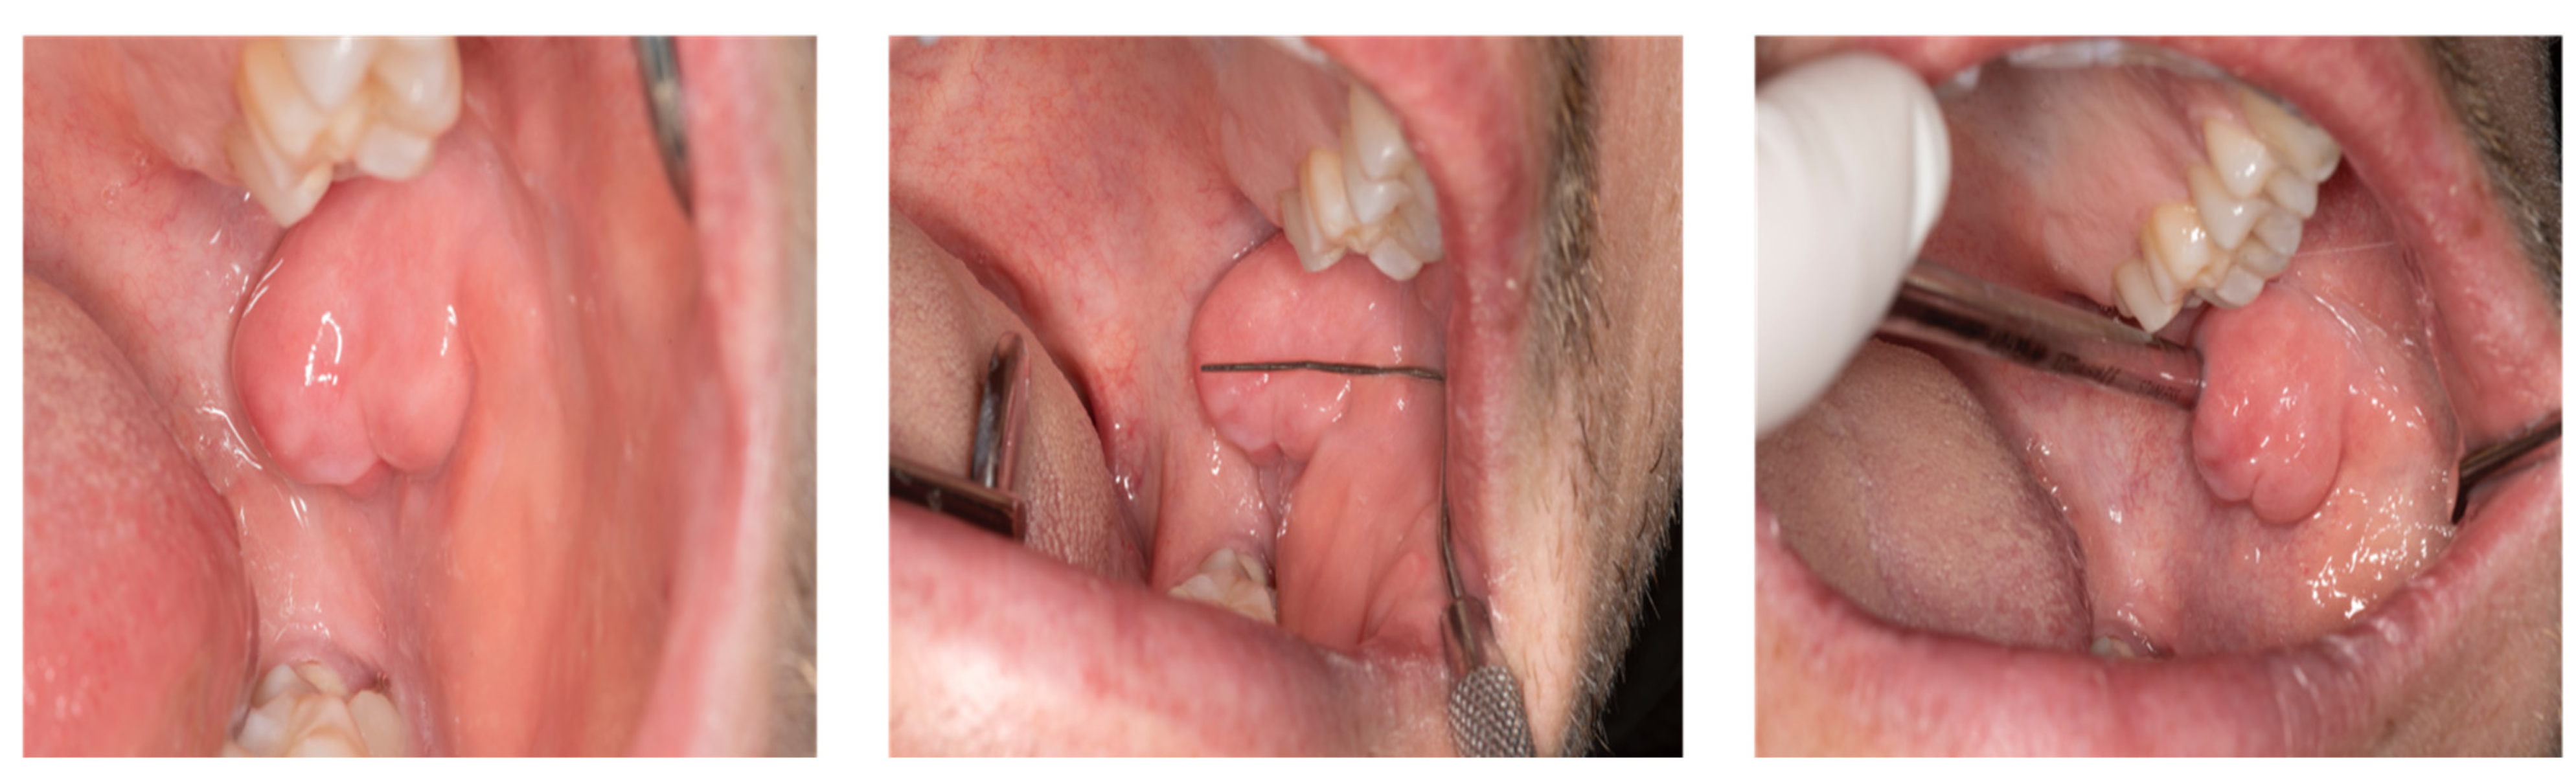

Intraoral clinical examination revealed a well-circumscribed, smooth-surfaced mobile, nodular swelling measuring approximately 2.3 × 2 cm in the left planum buccale, covered with normal pink mucosa. The lesion was hard and noncompressible on palpation, the temperature was not elevated, and the lymph nodes were neither enlarged nor palpable. In addition, no increased teeth mobility was observed in the affected region (Figure 1).

Figure 1.

Intraoral visualization of an abnormally large hyperplastic lesion originating from the buccal mucosa in a 28-year-old patient presenting to the Department of Oral and Maxillofacial Surgery. Besides a relatively rapid growth of lesion size over the past six months, a displacement of the maxillary second molar could be observed. In addition to the main complaints of pain and swelling, clinical examination revealed a well-circumscribed, smooth-surfaced, pinkish nodular swelling measuring 23 × 20 mm in the left planum buccale.